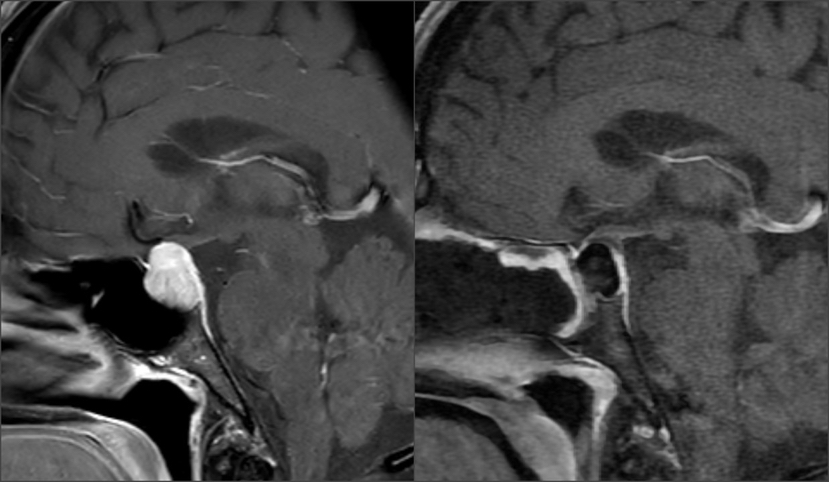

术前术后影像学对比

Knosp1级肿瘤,鞍隔被肿瘤推挤向上,冠状位略呈“雪人征”,术中鞍隔可能塌陷 T2信号较为均质,考虑肿瘤有一定韧性 垂体柄偏向左侧,残存垂体左侧更多,鞍隔面、鞍底面亦有薄层受压垂体组织,术中需注意保护,亦有助于辨认肿瘤与垂体之间的分界面